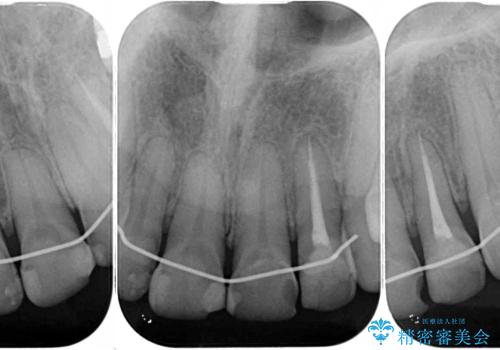

- 前歯の虫歯や治療跡が気になるとのことで来院された患者様です。

以前矯正治療をされ、その時には歯列が整ったので満足されたそうですが、若干の後戻りにより隙間ができ、矯正治療前に治療していた虫歯の跡が気になったため、オールセラミックによる審美治療を希望されました。

目立つ範囲である前歯4歯をオールセラミッククラウンにて補綴することとしました。